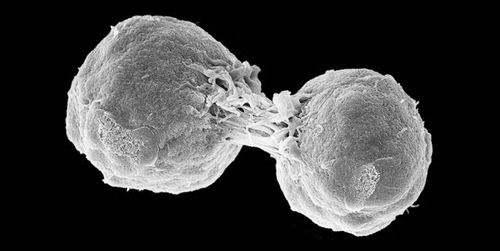

癌细胞是从正常细胞变来的,就像是坏人也是从好人变过来的,坏人变坏之前也是好人,但在变坏之后就与好人有不同了,癌细胞也一样,是从正常变过。